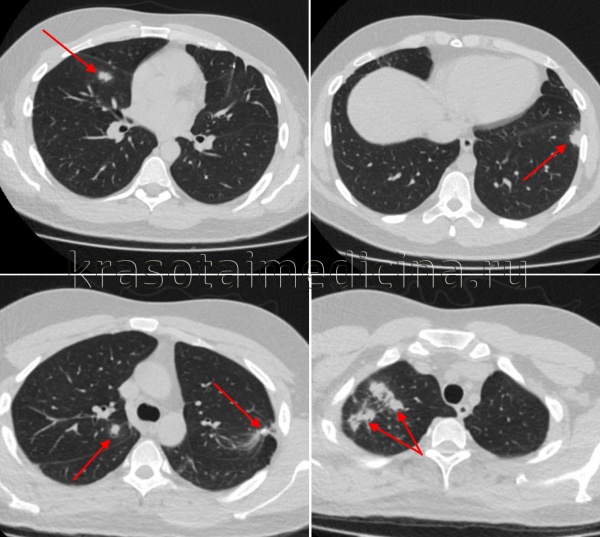

Рентгенологически преимущественно в прикорневых, верхних и средних, реже в нижних отделах одного или обоих легких определяются очаги разной величины, формы и интенсивности. При двустороннем процессе они расположены обычно асимметрично. Весьма характерна для диссеминированного лимфогенного туберкулеза рентгенологическая картина в виде петлистой деформации легочного рисунка, чаще всего в кортикальных, а также в прикорневых зонах, обусловленная лимфангитом и фиброзным утолщением стенок лимфатических сосудов в междольковых пространствах. Во внутригрудных лимфатических узлах часто обнаруживаются кальцинаты. Нередко одновременно наблюдается понижение прозрачности легкого, главным образом за счет лимфостаза или уплотнения костальной и междолевой плевры, реже из-за наличия небольшого количества жидкости в плевральных полостях.

- Рентгеносемиотика диссеминированного туберкулеза легких зависит от клинической формы заболевания. Признаками острого процесса служат наличие в обоих легочных полях множественных однотипных очагов, расположенных симметрично, в виде цепочки по ходу сосудов. При подострой диссеминации очаги имеют тенденцию к слиянию, возможно образование полостей распада. Для хронической диссеминации характерно асимметричное расположение очаговых теней, которые имеют разную форму, величину, очертания, интенсивность в зависимости от срока давности их возникновения. Рентгенография легких, как правило, дополняется линейной или компьютерной томографией.

КТ ОГК. Множественные очаговые поражения верхней и средней доли правого легкого, верхней и нижней доли левого легкого у пациента с диссеминированным туберкулезом.